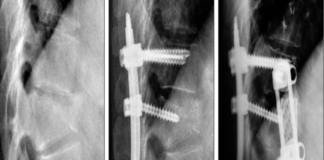

What is a Herniated Disc?

Discs of cartilage act as cushions between the vertebrae or bones in the spine. These cushions are known as intervertebral discs. When a disc...

Lower Back Pain

Lower Back Pain Treatment: What are Your Options?

Lower back pain is an ailment that affects a large number of people at some point in...